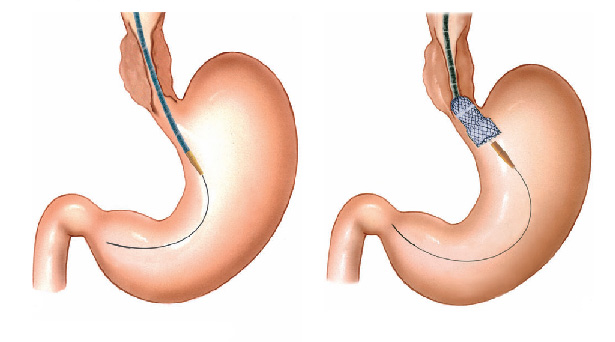

Pacientes que têm o objetivo de emagrecer, podem ter como alternativa a passagem de um balão intragástrico. A passagem do balão é realizada por endoscopia e o procedimento dura cerca de 20 a 30 minutos.

Passagem de Balão Intragástrico

1. O balão intragástrico é introduzido desinsuflado durante a endoscopia e colocado no estômago.

2. Um líquido azul (azul de metileno diluído em soro fisiológico) é colocado dentro do balão através de uma válvula. O volume varia entre 500-700 ml.

3. O aparelho de endoscopia é removido e o balão intragástrico pode ser deixado por um período de até 6 meses.

Pacientes que têm o objetivo de emagrecer, podem ter como alternativa a passagem de um balão intragástrico. A passagem do balão é realizada por endoscopia e o procedimento dura cerca de 20 a 30 minutos.

Passagem de Balão Intragástrico

1. O balão intragástrico é introduzido desinsuflado durante a endoscopia e colocado no estômago.

2. Um líquido azul (azul de metileno diluído em soro fisiológico) é colocado dentro do balão através de uma válvula. O volume varia entre 500-700 ml.

3. O aparelho de endoscopia é removido e o balão intragástrico pode ser deixado por um período de até 6 meses.